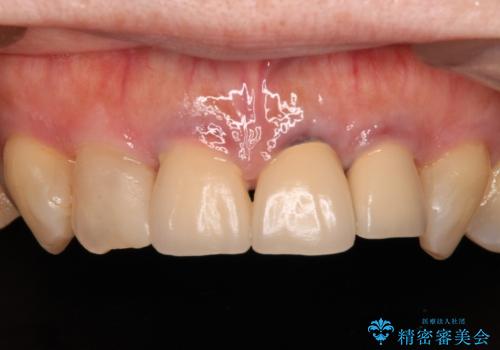

- 黄色みのある前歯のセラミックを、明るい色に替えたいとのことで来院された患者様です。

透明感がないことも気になっていたため、オールセラミッククラウンでは透けてしまう可能性のある金属の土台をファイバーコアに置き換え、1トーン明るいクラウンにて仕上げていくこととしました。

透明感のある自然な色合いとなり、患者様には大変満足していただけました。